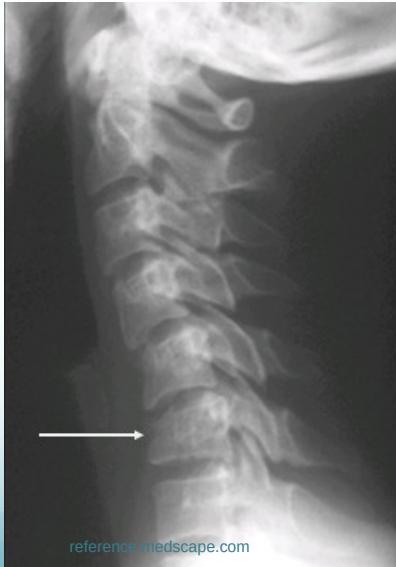

Lateral View

- All C- vertebrae & upper T1

- Prevertebral soft tissue width

- Four parallel curves

- Front of vertebral bodies

- Back of vertebral bodies

- Posterior borders of lateral masses

- Bases of spinous processes

Cervical Wedge-Compression Fracture

- Pure flexion injury

- Mid- & lower cervical

- Stable if only anterior column affected